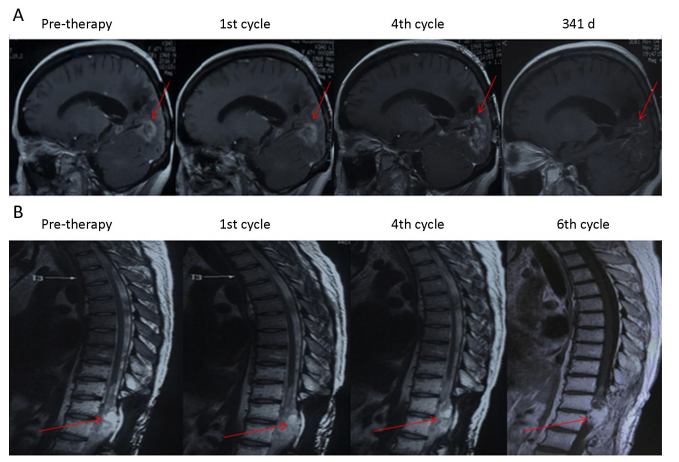

1、研究發(fā)現(xiàn),綠原酸治療對部分患者(P3P4)有效,使腫瘤病灶縮小,達到穩(wěn)定疾病狀態(tài)(SD)。P3P4的無進展生存期(PFS)分別為8.1個月和4.9個月,總生存期(OS)均超過16.5個月,且至今仍存活。

P3和P4患者綠原酸治療前后的磁共振成像(MRI)圖像